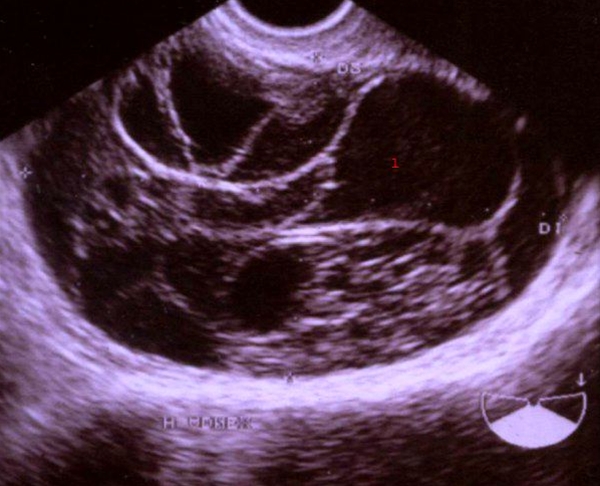

Ultralydskanning, musinøst cystadenom

Ultralydskanning af æggestok

Æggestok med fler-kamret cyste